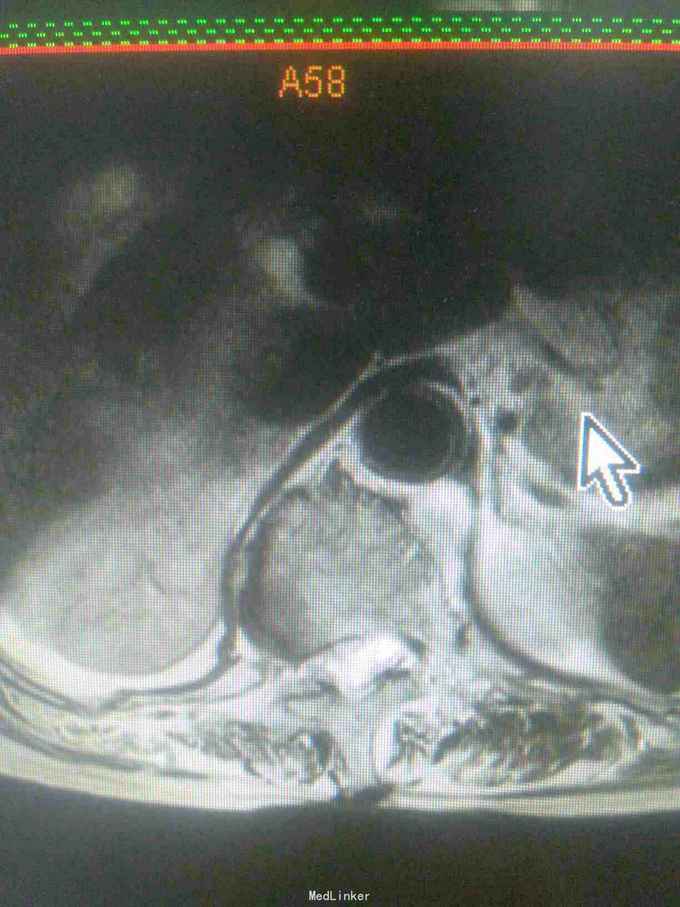

患者女,71岁,因双下肢无力,活动障碍5年余,不能行走半年。患者自诉于5年前无明显原因及诱因下逐渐出现双下肢无力,开始以双足部、双小腿为主,后整个下肢都感到无力,到入院半年前不能站立行走。大小便功能正常。

查体,双下肢肌肉萎缩,肌张力高,双侧大腿肌力3级,双小腿肌力2级,双足部肌力0级,双足部疼觉减退,会阴及双大腿、小腿感觉均正常,腱反射未引出,肛门反射、腹壁反射可引出,肛门括约肌未见松驰,双上肢查体正常。

目前诊断:双下肢瘫痪查因。

请教各位同行老师,这个考虑是什么问题,需要进一步完善什么检查。